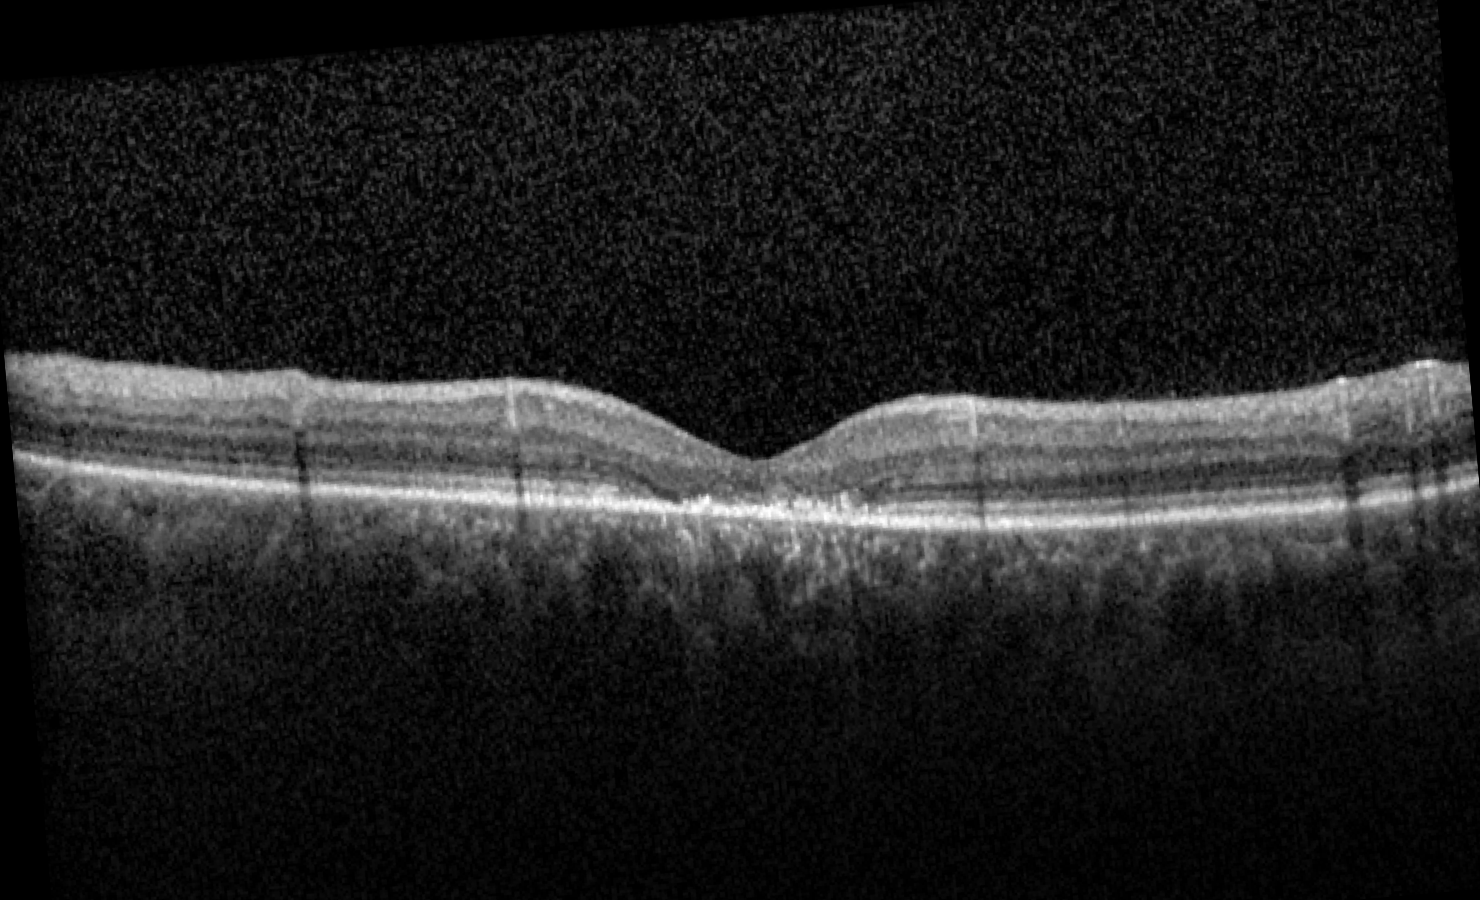

Case 6 is a 32 year old man with 20/150 visual acuity. He had relatively normal acuity as a young child but gradually lost vision after age 10. He is photophobic and cannot recognize any of the Ishihara pseudo-isochromatic plates. Two of his siblings as well as his mother and his maternal grandfather are all similarly affected.

Optical coherence tomogram of the left eye.